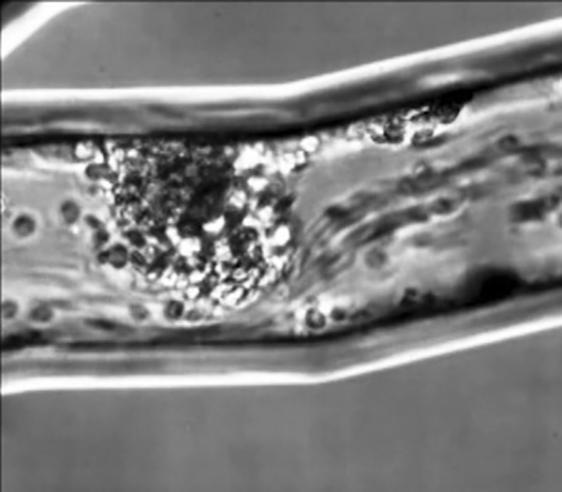

Human neutrophil clusters obstruct flow in a human lung endothelial model in response to a fungus (C. albicans)